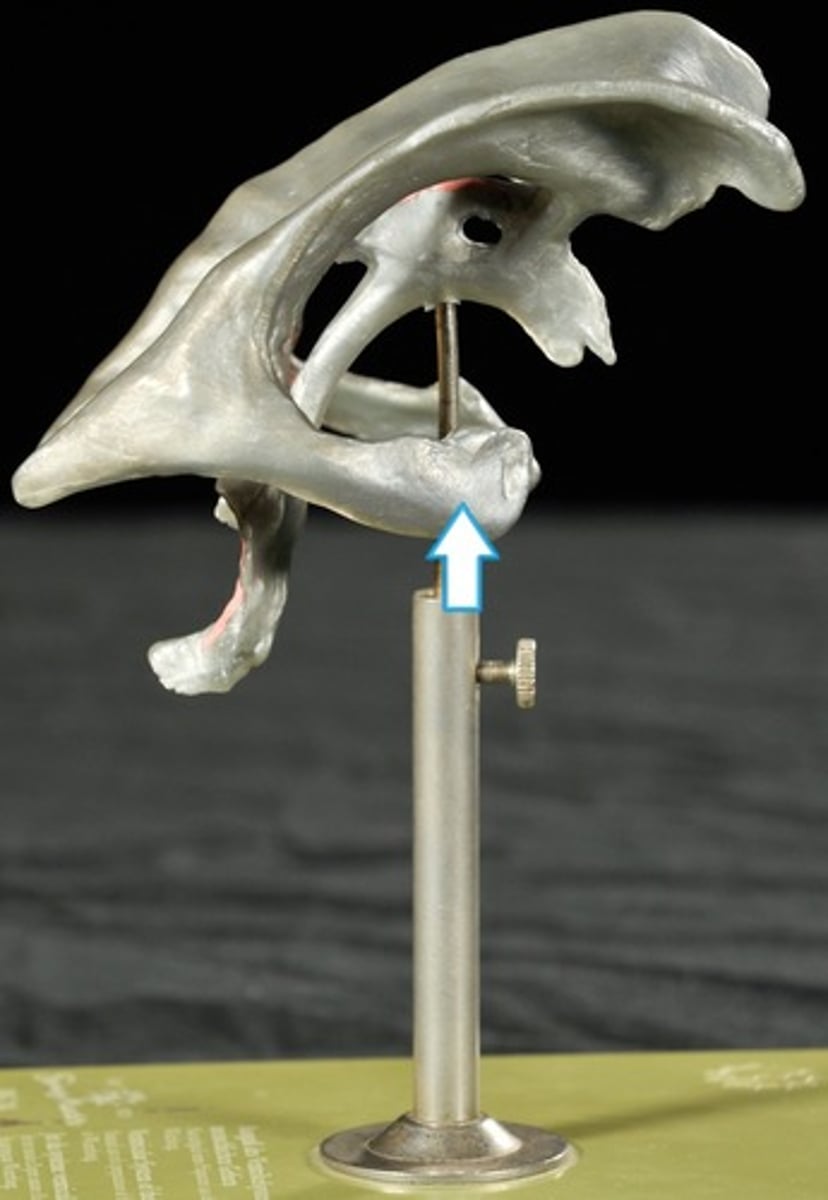

Traumatic brain injuries (head trauma)

1) a leading cause of accidental death in U.S.

2) Caused not only by localized injury at site of blow but also by ricocheting effect as brain hits opposite end of skull

Types of Head Trauma

Concussion,

Contusion,

Subdural Hematoma,

Cerebral Edema

Concussion

Alteration in brain function following blow to the head

Contusion

Bruising in the brain and can cause permanent Neurological Damage

Subdural Hematoma

Blood vessels are broken in the brain

Cerebral Edema

Swelling on the brain